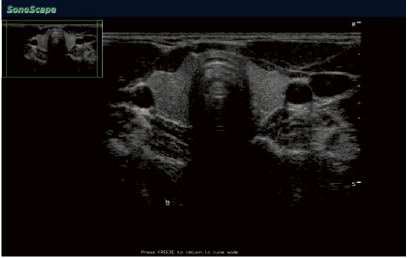

El sistema S40 también expresa su profunda preocupación por la salud de las mujeres y ofrece una solución integral de OB / GYN , proporcionando imágenes endovaginal superior, así como una imagen excelente fetal para 2D y adquisición 3D/4D .

3D en tiempo real (4D )

Con el aumento de canal físico y la nueva plataforma de S40, tanto en calidad de imagen y velocidad de fotogramas se reúnen un nuevo estándar de serie SonoScape S . Gracias a la alta velocidad de fotogramas y las tecnologías avanzadas , la proyección de imagen 4D de S40 proporciona un movimiento suave del feto y la oferta de adquisición integral 4D , la representación de datos y funcionalidad post- procesamiento.

3D/4D Endovaqinal transductor

Debido al reciente desarrollo 4D transductor endovaginal , S40 es capaz de detectar el más mínimo detalle de feto en el primer trimestre del embarazo mejora la fiabilidad del diagnóstico de los médicos . A excepción de la buena calidad de imagen 3D/4D , S40 también permite obtener imágenes excelentes 2D bajo el diagnóstico 3D/4D endovaginal , lo que aumenta la capacidad diagnóstica de los médicos clínicos y la satisfacción de las pacientes obstétricas.

Paciente orientada Sonda Endovaginal

S40 reduce la incomodidad y garantizar la seguridad de los pacientes de ginecología , ofreciendo sonda endovaginal orientada al paciente . 200 grados de ángulo visión : Alta densidad y la sonda endovaginal ángulo de exploración súper amplio proporciona más información de diagnóstico para los médicos , que no sólo aumenta la confianza diagnoisc de médicos sino que también reduce el dolor de los pacientes. Función de detección de temperatura: Esta función permite que el transductor que dejar de trabajar de forma automática cuando la temperatura dentro de los pacientes es superior a lo normal . Garantiza la seguridad de los pacientes en todo el diagnóstico. Diseño ergonómico: La ergonomía de S40 hace sonda endovaginal a realizarse con facilidad, y el ángulo de la sonda especialmente diseñado proporciona comodidad y la confianza de los médicos al realizar la biopsia.